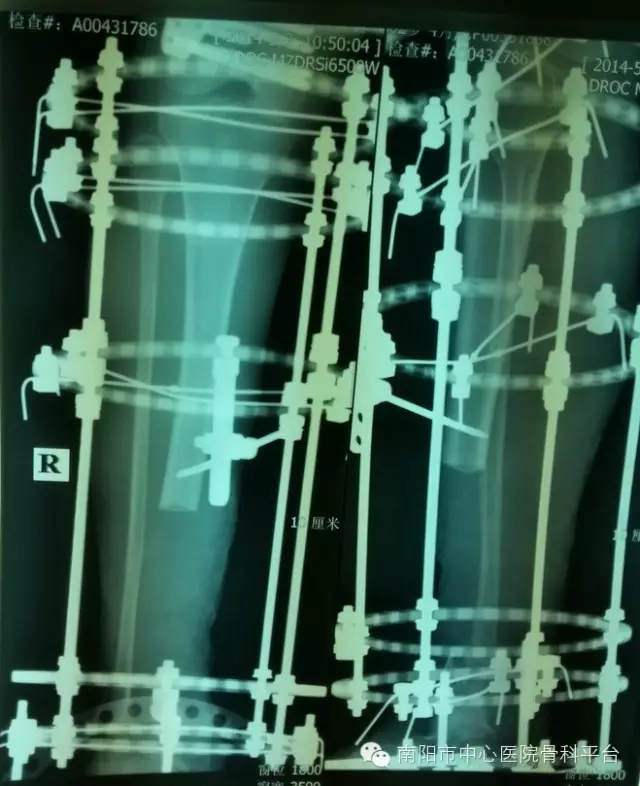

南阳市中心医院骨科一病区利用Ilizarov(伊利扎洛夫)技术,为多名患者实施了“骨搬运”手术,这一手术的成功标志着我院骨科在创伤修复方面又前进了一大步,也填补了我市的一项空白,现简单介绍一下这一神奇的技术,使大家了解从“替代修复重建”到“自然重建”这一医学新观念。

这一技术在骨科应用前景广泛,能够治疗复杂骨折、四肢畸形,骨不连、骨缺损、慢性骨髓炎、关节僵直、四肢短缩畸形等多种骨科疾病。在创伤骨科、矫形骨科、肢体延长方面有独特的效果,具有创伤小、疗效好,手术时间短、痛苦少、费用低等优势,在某些方面是其他方法不能比拟的。例如:美国做了一项慢性骨髓炎对比研究,与常规方法相比(如死骨切除、抗生素串珠、游离皮瓣、植骨),Ilizarov方法减少了并发症发生率,减少了手术和住院时间,提高了成功率,平均每个病人节约医疗费3万美元。